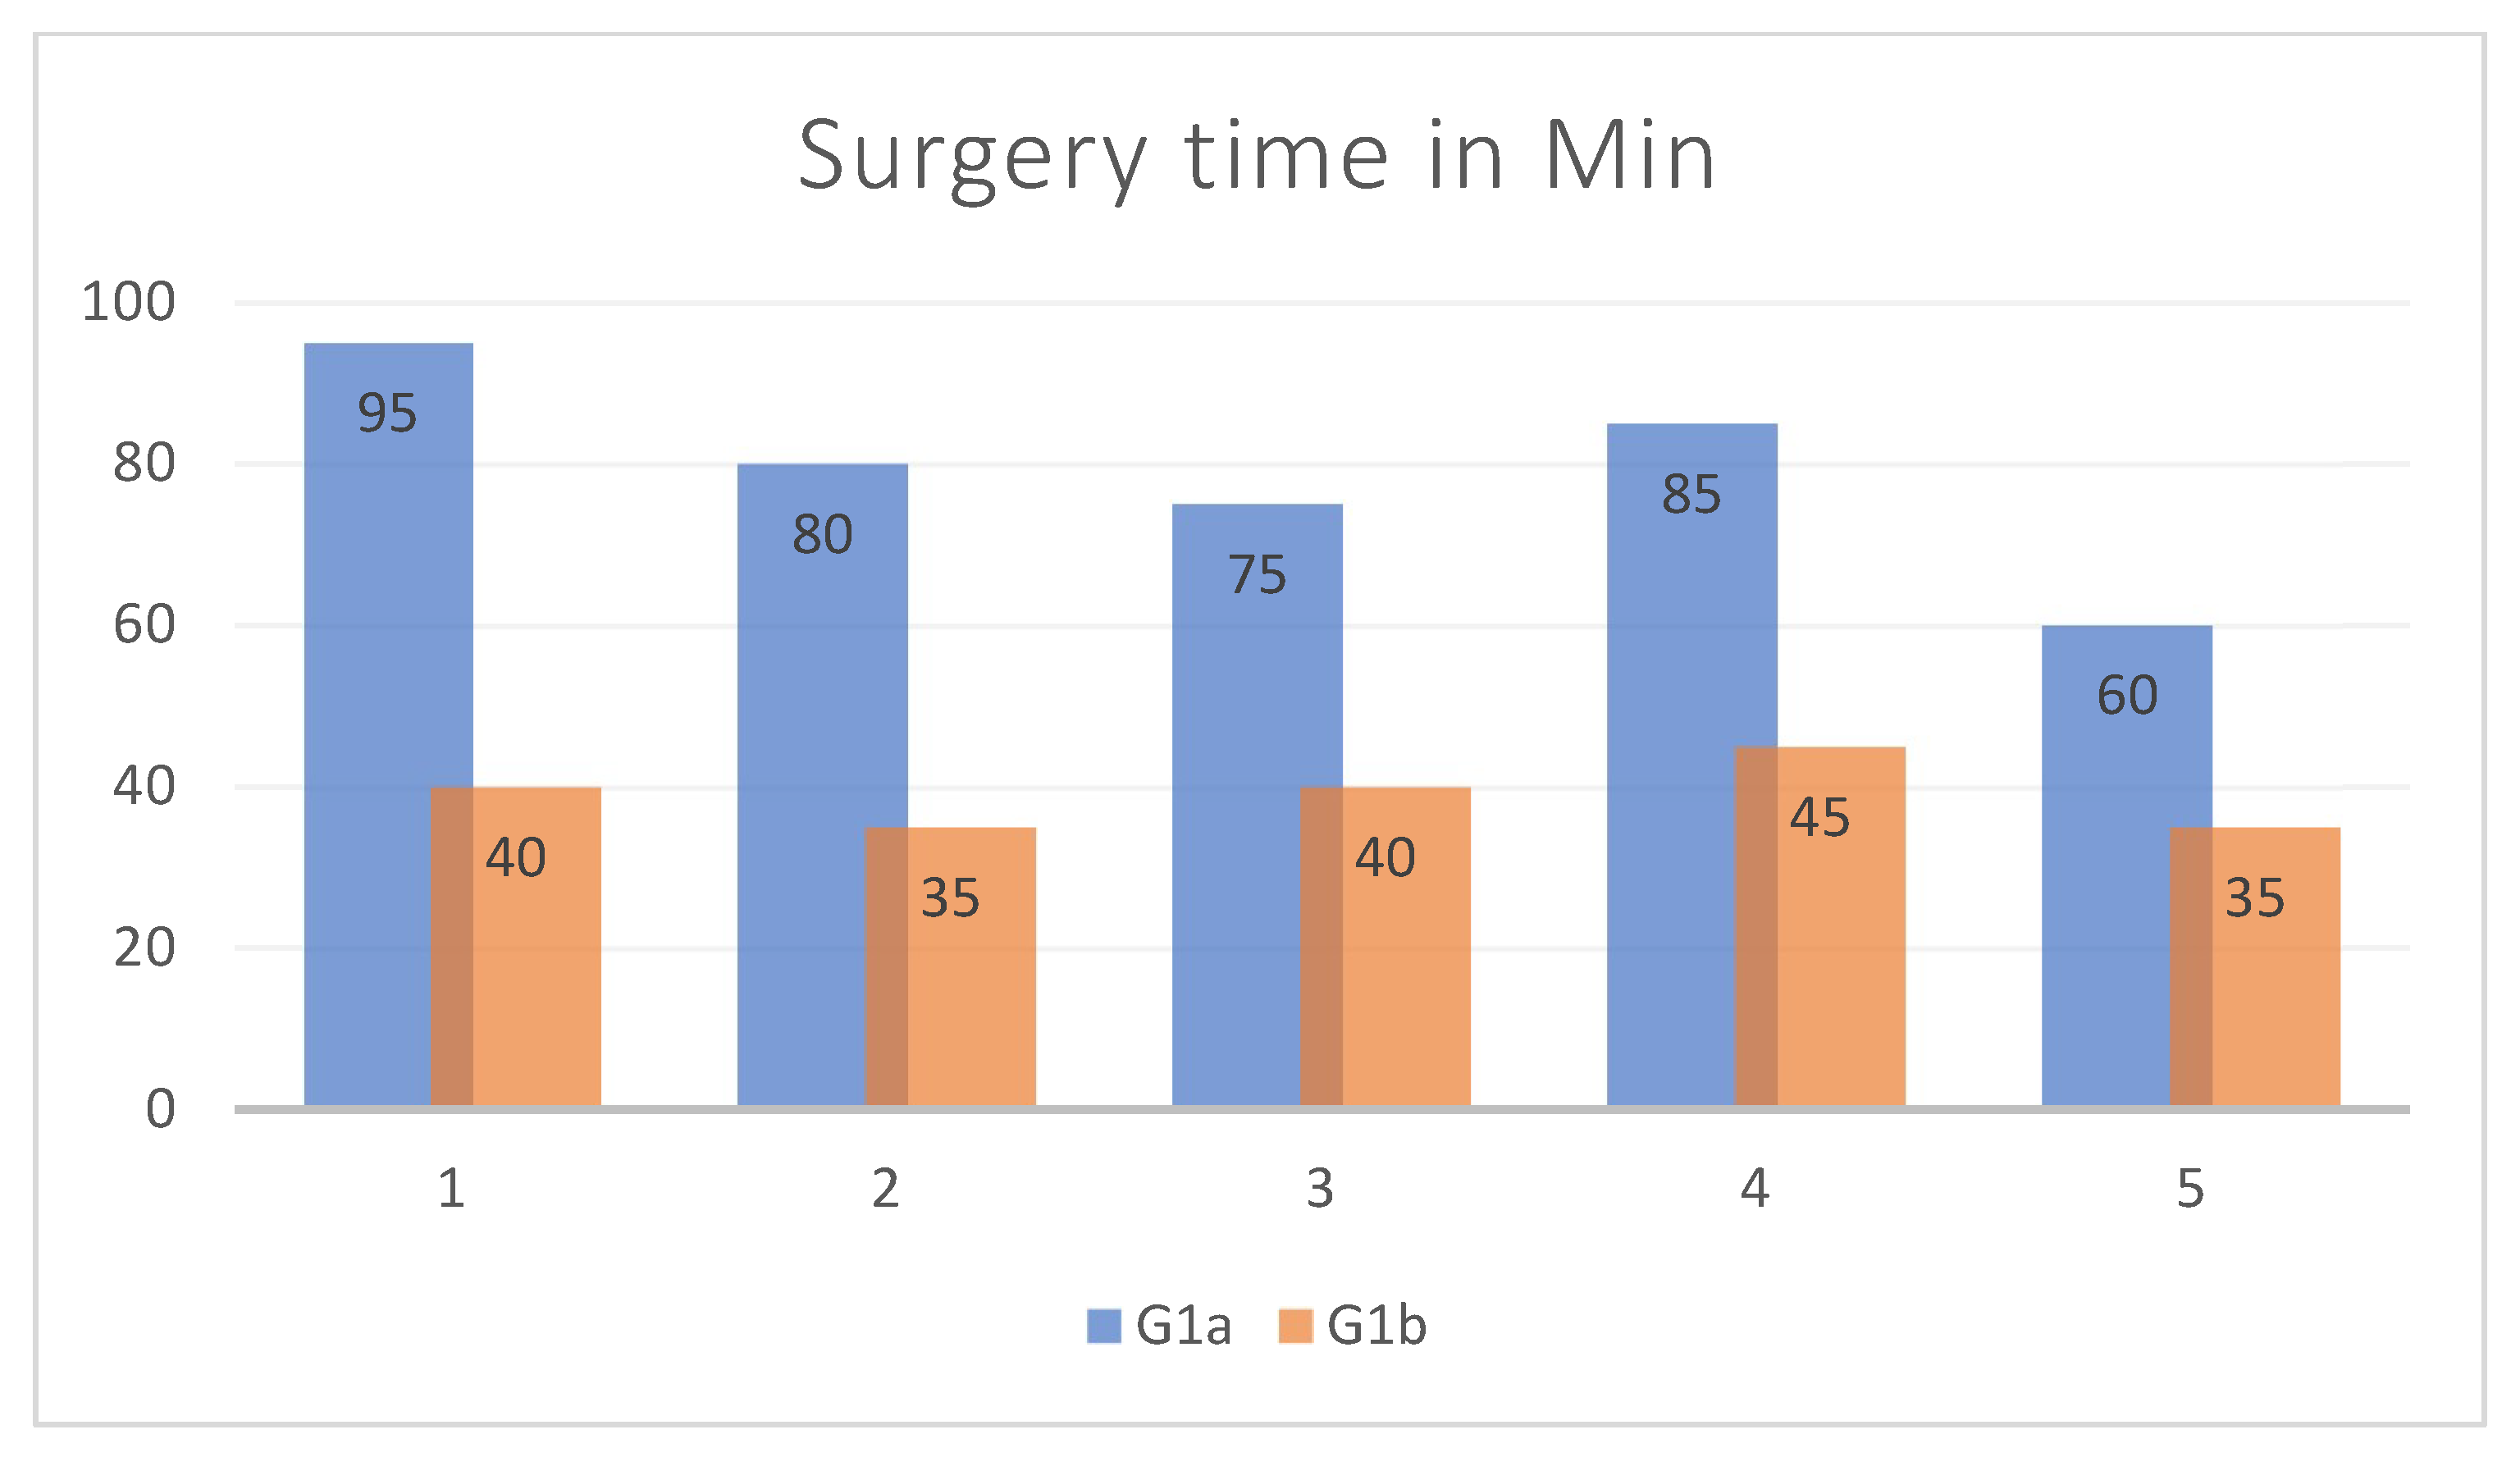

- Group 1 (G1): patients surgically treated for isolated OFF, divided into 2 subgroups: G1a (patients undergoing orbital floor reconstruction with an intraoperatively shaped mesh) and G1b (patients undergoing orbital floor reconstruction with a preoperative mesh shaped on a 3D-printed stereolithographic model, obtained from the patient’s CT scan and using the Ultimaker S5 3D printer—Manufat Engineering Srl, 160 23900 Lecco (LC), Italy).

3. Results

| Age | Sex | Type of Incidente | Fracture Side | Volume cm3 Right Orbit | Volume cm3 Left Orbit | Volume cm3 Mesh Orbit | Vol- cm3 Difference Pre-op | Vol- cm3 Difference Post-op | Vol- cm3 Recovery Difference | Surgery Time in Min | |

|---|---|---|---|---|---|---|---|---|---|---|---|

| 1 | 33 | Male | aggression | Right | 29.0359 | 25.5777 | 23.5814 | 3.4582 | 5.4545 | −1.9963 | 95 |

| 2 | 59 | Male | aggression | Right | 23.9741 | 21.2927 | 20.5365 | 2.6814 | 3.4376 | −0.7562 | 80 |

| 3 | 37 | Male | car accident | Left | 23.204 | 27.6138 | 24.7729 | 4.4098 | 2.8409 | 1.5689 | 75 |

| 4 | 74 | Male | accidental fall | Left | 25.2797 | 26.4807 | 24.145 | 1.201 | 2.3357 | −1.1347 | 85 |

| 5 | 41 | Male | aggression | Left | 25.9815 | 27.0248 | 24.6445 | 1.0433 | 2.3803 | −1.337 | 60 |

| Age | Sex | Type of Incidente | Fracture Side | Volume cm3 Right Orbit | Volume cm3 Left Orbit | Volume cm3 Mesh Orbit | Vol- cm3 Difference Pre-op | Vol- cm3 Difference Post-op | Vol- cm3 Recovery Difference | Surgery Time in Min | |

|---|---|---|---|---|---|---|---|---|---|---|---|

| 1 | 19 | Male | sports trauma | Right | 27.6954 | 24.8297 | 25.1231 | 2.8657 | 2.5723 | 0.2934 | 40 |

| 2 | 72 | Male | car accident | Left | 24.0521 | 28.3124 | 23.5679 | 4.2603 | 4.7445 | −0.4842 | 35 |

| 3 | 37 | Male | aggression | Right | 21.9546 | 26.0827 | 21.7928 | 4.1281 | 4.2899 | −0.1618 | 40 |

| 4 | 30 | Male | sports trauma | Left | 21.7904 | 24.7852 | 22.2585 | 2.9948 | 2.5267 | 0.4681 | 45 |

| 5 | 19 | Male | sports trauma | Left | 31.149 | 32.1745 | 30.4723 | 1.0255 | 1.7022 | −0.6767 | 35 |